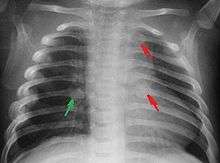

The material factual allegations of the amended complaint are as follows. Plaintiff was born on May 14, 1970. On repeated occasions during the first year of her life she was severely beaten by her mother and the latter’s common law husband, one Reyes. On April 26, 1971, when the plaintiff was eleven months old, her mother took her to the San Jose Hospital for examination, diagnosis, and treatment. The attending physician was defendant Dr. Flood, acting on his own behalf and as agent of the defendant San Jose Hospital. At the time, the plaintiff was suffering from a comminuted spiral fracture of the right tibia and fibula, which gave the appearance of having been caused by a twisting force. Plaintiff’s mother had no explanation for this injury. Plaintiff had bruises over her entire body. In addition, she had a non-depressed linear skull fracture which was then in the process of healing. Plaintiff demonstrated fear and apprehension when approached. Inasmuch as all plaintiff's injuries gave the appearance of having been intentionally inflicted by other persons, she exhibited the medical condition known as the battered child syndrome.

It is alleged that proper diagnosis of plaintiff's condition would have included taking X-rays of her entire skeletal structure, and that such procedure would have revealed the fracture of her skull. Defendants negligently failed to take such X-rays, and thereby negligently failed to diagnose her true condition. It is further alleged that proper medical treatment of plaintiff's battered child syndrome would have included reporting her injuries to local law enforcement authorities or juvenile probation department. Such a report would have resulted in an investigation by the concerned agencies, followed by a placement of plaintiff in protective custody until her safety was assured. Defendants negligently failed to make such report.

The complaint avers that as a proximate result of the foregoing negligence plaintiff was released from the San Jose Hospital without proper diagnosis and treatment of her battered child syndrome, and was returned to the custody of her mother and Reyes who resumed physically abusing her until she sustained traumatic blows to her right eye and back, puncture wounds over her left lower leg and across her back, severe bites on her face, and second and third degree burns on her left hand.

On July 1, 1971, plaintiff was again brought in for medical care, but to a different doctor and hospital. Her battered child syndrome was immediately diagnosed and reported to local police and juvenile probation authorities, and she was taken into protective custody. Following hospitalization and surgery she was placed with foster parents, and the latter subsequently undertook proceedings to adopt her. Plaintiff's mother and Reyes fled the state, but were apprehended, returned for trial, and convicted of the crime of child abuse.[1]

While helpful, the foregoing general history of the battered child syndrome is not conclusive on the precise question in the case at bar. The question is whether a reasonably prudent physician examining this plaintiff in 1971 would have been led to suspect she was a victim of the battered child syndrome from the particular injuries and circumstances presented to him, would have confirmed that diagnosis by ordering X-rays of her entire skeleton, and would have promptly reported his findings to appropriate authorities to prevent a recurrence of the injuries. There are numerous recommendations to follow each of these diagnostic and treatment procedures in the medical literature cited above.

For example, the leading article by Kempe et al., op. cit., supra,[9] states that "A physician needs to have a high initial level of suspicion of the diagnosis of the battered-child syndrome in instances of subdural hematoma, multiple unexplained fractures at different stages of healing, failure to thrive, when soft tissue swelling or skin bruising are present, or in any other situation where the degree and type of injury is at variance with the history given regarding its occurrence . . . ." (Id., at p. 20.) Of the different types of fractures exhibited, an arm or leg fracture caused by a twisting force is particularly significant because "The extremities are the 'handles' for rough handling" of the child by adults. (Id., at p. 22.) The article also contains numerous recommendations to conduct a "radiologic examination of the entire skeleton" for the purpose of confirming the diagnosis, explaining that "To the informed physician, the bones tell a story the child is too young or too frightened to tell." (Id., at p. 18.) Finally, on the subject of management of the case it is repeatedly emphasized that the physician "should report possible willful trauma to the police department or any special children's protective service that operates in his community" (id., at p. 23) in order to forestall further injury to the child: "All too often, despite the apparent cooperativeness of the parents and their apparent desire to have the child with them, the child returns to his home only to be assaulted again and suffer permanent brain damage or death." (Id., at p. 24.)